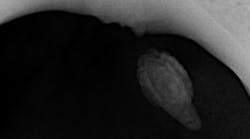

During an oral cancer screening, a soft-tissue lesion was noted on the floor of the mouth at the junction of the ventral surface of the tongue (figure 1).

The lesion was offset to the left, but appeared to cross the midline based upon the position of the frenum. The lesion was about 1.5 cm x 1 cm. Upon palpation, the tissue was firm but not indurated and mobile as one mass. The patient reported no symptoms other than mild discomfort upon palpation (figure 2). When asked about the duration of the lesion, the patient stated he had been aware of it for around two to three weeks, but it was not bothering him.